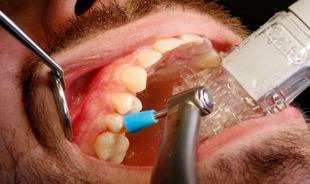

Step 1-Cleaning the surface of the tooth to be treated. Before the start of treatment, clean the affected tooth and adjacent teeth. Remove any cleaning residue with water spray. Create a sufficiently dry working field. You should take appropriate measures such as rubber dam, liquid dam or similar to protect the gingival tissue (Fig. 2).

Step 2-Isolation of the treatment site. Along with Isolite, use of DMG’s MiniDam offers a fast and convenient means for isolating a single proximal area while helping to maintain a dry field. Here the device is placed with the aid of dental floss, allowing quick placement into the proximal area (Fig. 3).